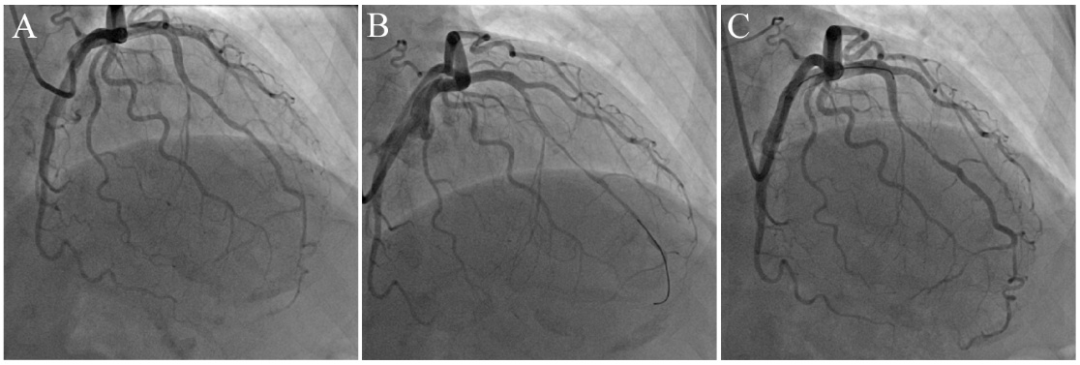

前降支中段肌桥段可疑狭窄(A),拟行IVUS检查。导丝通过后肌桥段痉挛(B),注射硝酸甘油后缓解(C)。

图10 IVUS导管诱发冠脉痉挛。

前降支中段肌桥段可疑狭窄(A),行IVUS检查后肌桥段痉挛(B),注射硝酸甘油后缓解(C)。